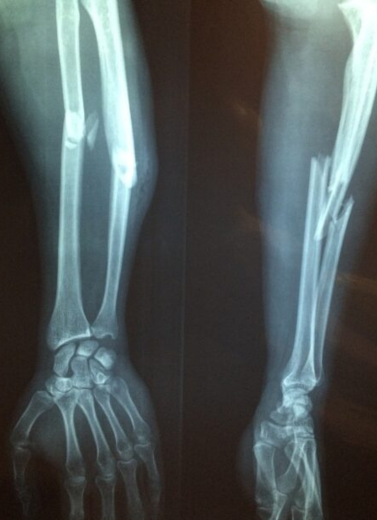

Post-Traumatic Deformities

Malunions and Nonunions of Bones

High success rate for old and neglected fractures